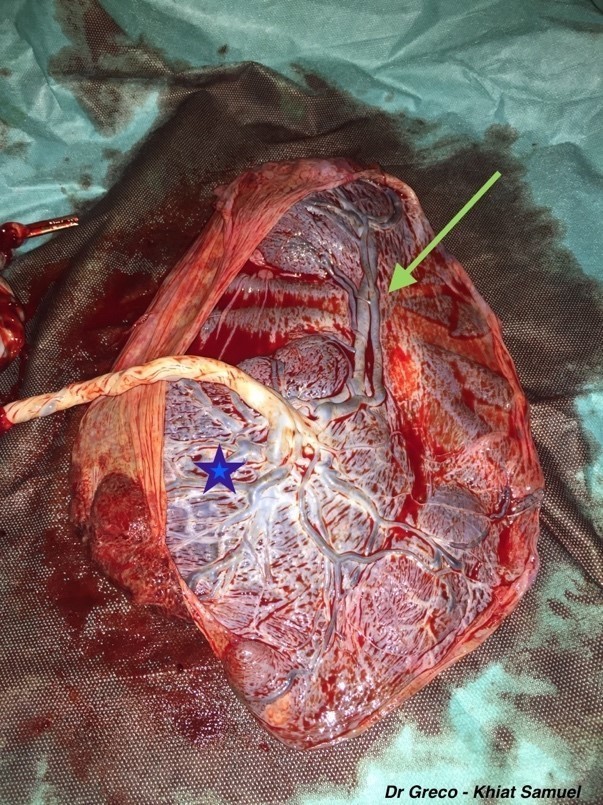

Vous réalisez la délivrance et retrouvez ceci :

Question 15 : Quelles sont les réponses vraies ?

La face qui comporte le cordon est la face fœtale du placenta

Au bout des vaisseaux courant sur les membranes, on peut voir une seconde masse placentaire correspondant à un cotylédon aberrant

En cas de rupture des membranes qui serait survenue au niveau des vaisseaux insérés sur les membranes, l’hémorragie de Benckiser peut survenir